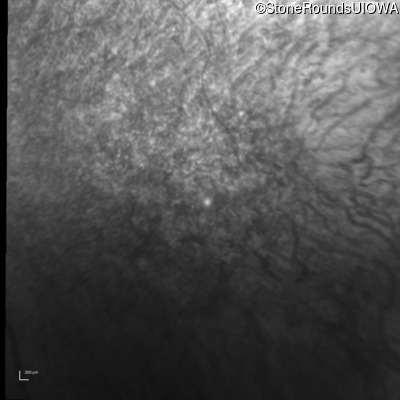

Infrared Fundus Photograph - Left - 10/100 -2

Exemplar